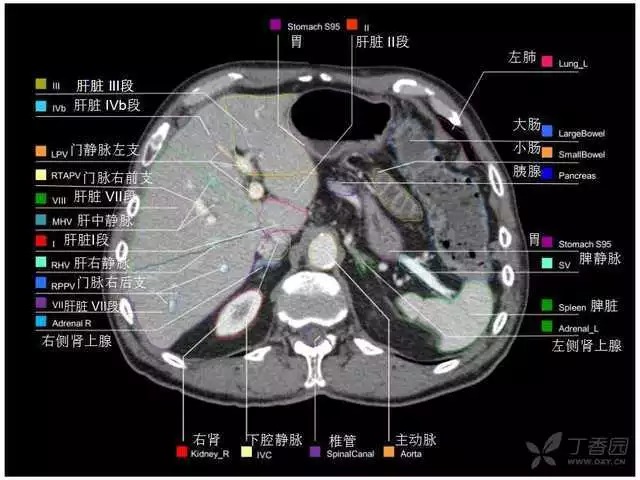

腹部肝脏高清CT断层的图谱

全腹部高清CT图谱,淋巴结彩色图谱,血管解剖图谱大汇总!

肝段,肝内管道的分布规律

美国放射学会ACR官网,对肝脏的区域和节段解剖学概述